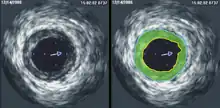

Intravascular ultrasound (IVUS) uses a specially designed catheter with a miniaturized ultrasound probe attached to its distal end, which is then threaded inside a blood vessel. The proximal end of the catheter is attached to computerized ultrasound equipment and allows the application of ultrasound technology, such as a piezoelectric transducer or capacitive micromachined ultrasonic transducer, to visualize the endothelium of blood vessels in living individuals.[11]